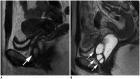

Magnetic resonance imaging is the optimal modality for pelvic imaging. It is based on T2-weighted magnetic resonance (MR) sequences allowing uterine and vaginal cavity assessment as well as rectal evaluation. Anatomical depiction of these structures may benefit from distension, and conditions either developing inside the lumen of cavities or coming from the outside may then be better delineated and localized. The need for distension, either rectal or vaginal, and the way to conduct it are matters of debate, depending on indication for which the MR examination is being conducted. In this review, we discuss advantages and potential drawbacks of this technique, based on literature and our experience, in the evaluation of various gynecological and rectal diseases.